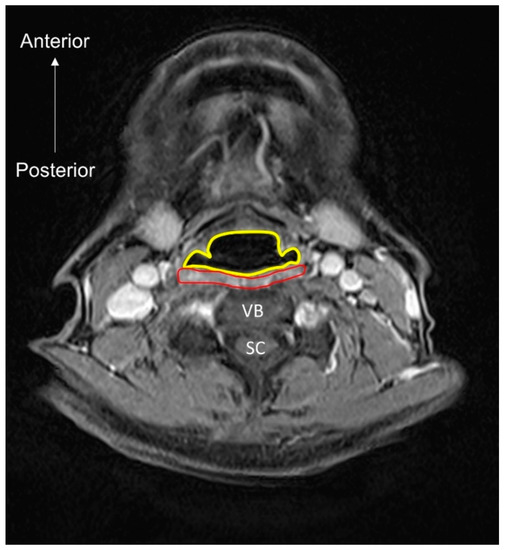

- Nakao, Y.; Uchiyama, Y.; Honda, K.; Yamashita, T.; Saito, S.; Domen, K. Age-related composition changes in swallowing-related muscles: A Dixon MRI study. Aging Clin. Exp. Res. 2021. [Google Scholar] [CrossRef]

- Nakao, Y.; Yamashita, T.; Honda, K.; Katsuura, T.; Hama, Y.; Nakamura, Y.; Ando, K.; Ishikura, R.; Kodama, N.; Uchiyama, Y.; et al. Association Among Age-Related Tongue Muscle Abnormality, Tongue Pressure, and Presbyphagia: A 3D MRI Study. Dysphagia 2021, 36, 483–491. [Google Scholar] [CrossRef]